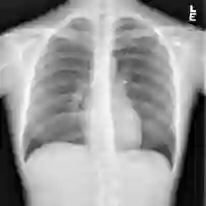

Chest X-ray (CXR) is the most typical radiological exam for diagnosis of various diseases. Due to the expensive and time-consuming annotations, detecting anomalies in CXRs in an unsupervised fashion is very promising. However, almost all of the existing methods consider anomaly detection as a One-Class Classification (OCC) problem. They model the distribution of only known normal images during training and identify the samples not conforming to normal profile as anomalies in the testing phase. A large number of unlabeled images containing anomalies are thus ignored in the training phase, although they are easy to obtain in clinical practice. In this paper, we propose a novel strategy, Dual-distribution Discrepancy for Anomaly Detection (DDAD), utilizing both known normal images and unlabeled images. The proposed method consists of two modules, denoted as A and B. During training, module A takes both known normal and unlabeled images as inputs, capturing anomalous features from unlabeled images in some way, while module B models the distribution of only known normal images. Subsequently, the inter-discrepancy between modules A and B, and intra-discrepancy inside module B are designed as anomaly scores to indicate anomalies. Experiments on three CXR datasets demonstrate that the proposed DDAD achieves consistent, significant gains and outperforms state-of-the-art methods. Code is available at https://github.com/caiyu6666/DDAD.